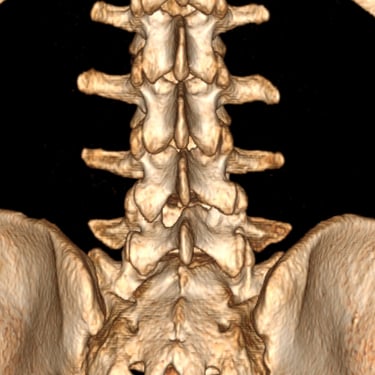

El síndrome postdiscectomía se presenta cuando persiste o reaparece el dolor lumbar y radicular después de una cirugía previa de hernia discal. Puede estar asociado a inestabilidad segmentaria, fibrosis epidural o degeneración discal progresiva. Cuando el manejo conservador no logra aliviar los síntomas, la fusión intersomática transforaminal (TLIF) mínimamente invasiva constituye una alternativa eficaz. Este procedimiento permite descomprimir las estructuras nerviosas, restaurar la altura discal y estabilizar el segmento afectado con menor daño muscular. La técnica mínimamente invasiva favorece menor sangrado, recuperación más rápida y mejores resultados funcionales.